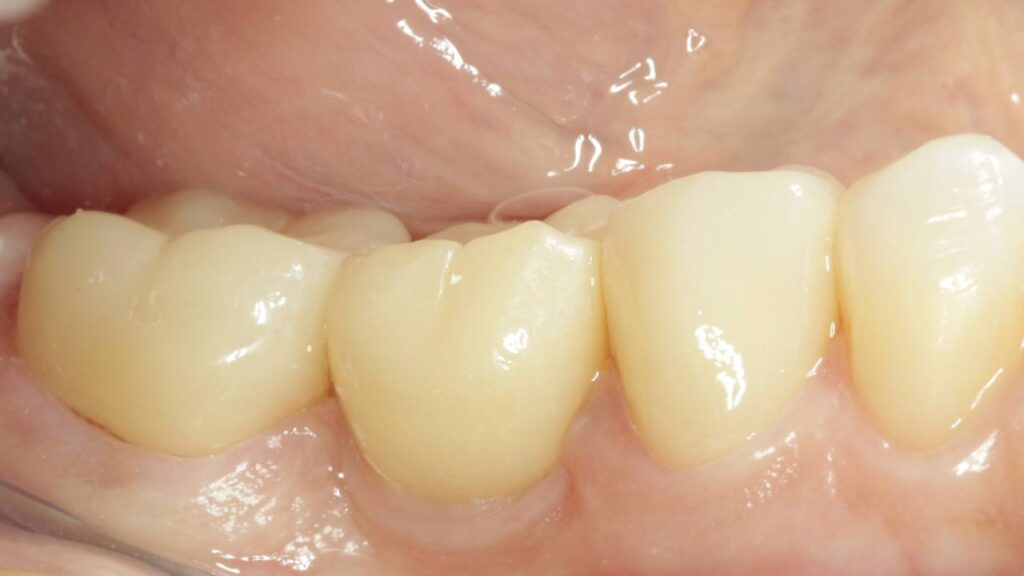

Протезирование коронками из диоксида циркония, после эндодонтического лечения — Исламов Л.А.(01.04.2026)